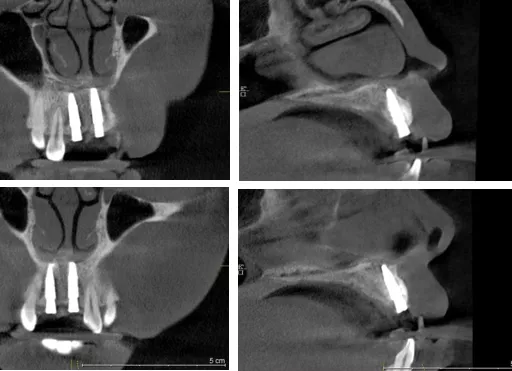

·      计划术区沿牙槽嵴顶做直线切口,翻瓣计划植入Straumann BLT 3.3*12mm各一枚。分别上3.6*5愈合基台。

术后影像学检查

种植体的选择

讨论:采用较细直径种植体进行前牙种植可以确保唇侧足够的骨厚度,同时钛锆合金的材质能确保小直径植体的强度。